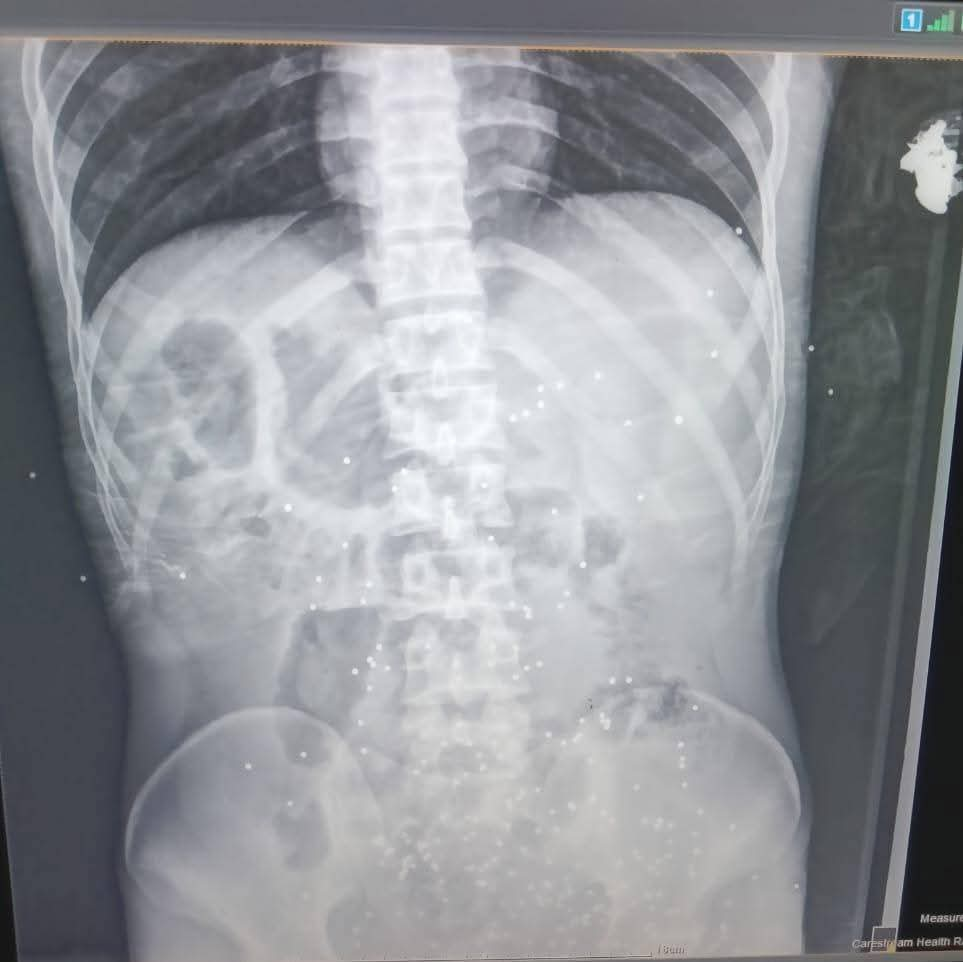

أعلنت الدكتورة نادية مكرم وكيلة وزارة الصحة بالمنيا بانه في الساعات الأولى من عيد الاضحي المبارك حضر إلى طوارىء مستشفي ملوي التخصصي شاب في العقد الثالث من العمر فى حالة سيئة نتيجه حادث طلق ناري خرطوش بالبطن.

مما أدى إلى إصابات متعدده بالبطن واشتباه اصابه بالوريد المغذى للطرف السفلى واشتباه اصابه فى المثانه ونزيف شديد من أماكن دخول الخرطوش، وتم دخول المريض إلى العمليات مباشره ،وتم عمل استكشاف بالبطن حيث تبين وجود نزيف داخلى بالبطن وإصابات بالامعاء ومساريقا البطن ومنديل البطن.